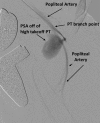

Coil embolization of an aberrant posterior tibial artery pseudoaneurysm after total knee arthroplasty

Arterial injury is a recognized but rare complication of total knee arthroplasty. These injuries, however, can be exceptionally devastating and potentially result in limb loss. Presentation may be delayed with symptoms associated with mass effect rather than with ischemia. We describe treatment of a patient with presentation delayed 2 weeks. In addition, the patient's arterial branch pattern demonstrated aberrant anatomy with high takeoff of the posterior tibial artery. This patient was successfully treated with transcatheter coil embolization. The current treatment options and published literature are reviewed.